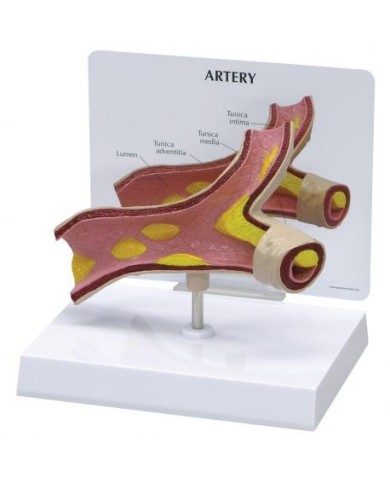

Su base removibile